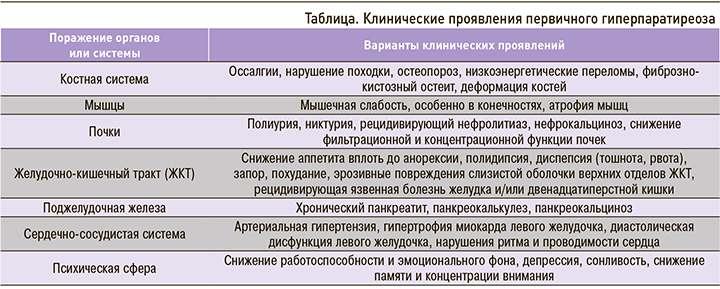

Согласно современной классификации, выделяют бессимптомную и симптомную (манифестную) формы ПГПТ [1]. Клинические проявления заболевания чрезвычайно разнообразны, они включают костные, мышечные, почечные, гастроэнтерологические, кардиоваскулярные и нейрокогнитивные расстройства (табл.).

Симптоматика гиперпаратиреоза в большинстве случаев пропорциональна выраженности гиперкальциемии [4]. Так, при сывороточном уровне общего кальция менее 3,0 ммоль/л жалобы пациентов неспецифичны – это общая и мышечная слабость, повышенная утомляемость, эмоциональная лабильность. Персистирующая гиперкальциемия в пределах 3,0–3,5 ммоль/л также протекает с минимальной симптоматикой, а быстропрогрессирующая гиперкальциемия, превышающая этот диапазон, сопровождается ухудшением состояния и сопряжена с развитием гастроэнтерологических, урологических, костных, кардиоваскулярных проявлений и осложнений.

Поражения со стороны опорно-двигательного аппарата при гиперпаратиреозе традиционно считаются наиболее частыми, очевидными и клинически значимыми. Причем эти нарушения вовсе не ограничиваются поражением только костной ткани, они включают чрезвычайно разнообразный спектр патологических изменений и в мышцах, и в суставах [5, 6]. Так, Pappu R. et al., проанализировав скелетно-мышечные симптомы у 74 пациентов с диагностированным ПГПТ, отметили, что среди суставных проявлений наиболее часто отмечались хондрокальциноз с отложением кристаллов гидроксиапатита кальция или без него (в 17,7% случаев), артралгии (15,2%) и неспецифический синовит (в 9,7%) [7]. В исследовании Н.Г. Мокрышевой было показано, что при ПГПТ практически одинаково часто встречается поражение суставов, мышц и костей (58, 46 и 66% соответственно) [8]. При этом в большей степени наблюдалось поражение крупных суставов (в 88% случаев) по сравнению с мелкими (в 12%).

К одному из проявлений суставной патологии при ПГПТ относят хондрокальциноз (частота встречаемости от 9 до 40% случаев) [6], который также служит одним из основных классификационных критериев болезни депонирования кристаллов пирофосфата кальция (ПФК) [9]. Согласно современной классификации этого заболевания, выделяют 4 его фенотипа: 1) бессимптомное депонирование кристаллов ПФК; 2) остеоартрит с депонированием кристаллов ПФК (ранее для обозначения этой формы использовался термин «псевдоостеоартроз»); 3) острый артрит с кристаллами ПФК («псевдоподагра»); 4) хронический артрит с кристаллами ПФК («псевдоревматоидный артрит») [10]. Последний фенотип болезни, как правило, представлен олиго- или полиартритом с симметричным поражением суставов, в том числе мелких, с утренней скованностью, припухлостью и нередко с повышением острофазовых показателей, перемежающимся вспышками артрита с характерными признаками кристаллического воспаления. Описанная клиническая картина хронического артрита схожа с симптоматикой ревматоидного артрита (РА), что может стать причиной поздней диагностики болезни депонирования кристаллов ПФК. В свою очередь, болезнь депонирования кристаллов ПФК может выступать не самостоятельным заболеванием, а проявлением гиперпаратиреоза, обусловленного аденомой ОЩЖ.